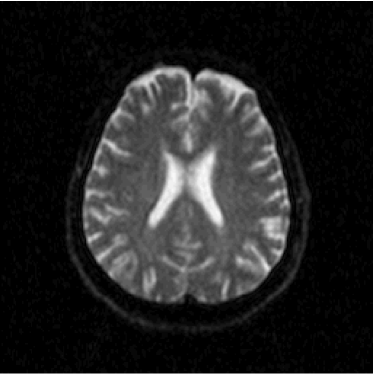

The diffusion-weighted magnetic resonance (MR) images were acquired from the clinical images database of the Laboratory of MR Images, at the Physics Department of Universidade Federal de Pernambuco, Recife, Brazil. The image database is composed by real clinical images acquired from a clinical MR tomographer of 1.5 T. The MR images used in this work corresponds to an unique volunteer with Alzheimer’s. As a case study there were used 80 DW-MR images, corresponding to 4 volumes of 20 axial slices, where one of these volumes is composed by ADC maps. All of these images correspond to a 70-year-old male patient with Alzheimer’s disease, with the following diffusion exponents: 0 s/mm2, 500 s/mm2 and 1000 s/mm2.

Figure 3: Axial DW-MR image of 13th slice with diffusion exponent of 1000 s/mm2

To perform the training we chose 13th slice of each volume sample (figures 1, 2 and 3), once this slice shows the temporal corni of the lateral ventriculi. The exhibition of such structures facilitates the analysis of the specialist and helps him to find a correlation between data generated by our computational tool and a priori specialist knowledge. Furthermore, slice 13 presents a considerable amount of artifacts out of the cranial region.